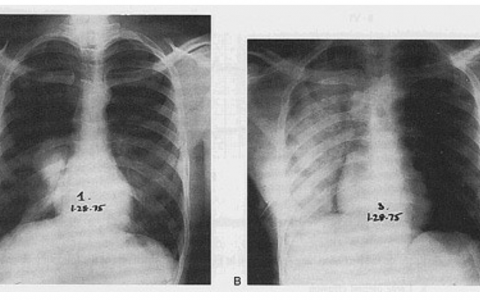

After a week of failed SBT, a tracheostomy tube is placed and she is able to ambulate. Bronchoscopy shows well-healing bronchial anastomosis without debris in the airways. Breath sounds are clear. She is able to participate in physical rehabilitation, but attempts to wean her from the ventilator are met with hypercapnia and tachypnea. The chest radiograph shown below has been unchanged since postoperative day two.

该患者有右侧膈肌功能障碍,这可能是其手术的并发症。在胸外科手术中,膈神经可被拉伸、压碎或无意中横断。测量膈肌偏移的无创方法是透视sniff test,指导患者深呼吸,然后以直立位sniff test,再次以侧卧位sniff test。深吸气时受累膈肌缺乏尾侧运动,sniff test时出现反常运动是阳性发现。该试验在单侧膈肌功能障碍中的假阳性率约为6%,对双侧膈肌功能障碍没有帮助。潜在治疗包括临时呼吸机支持、膈肌折叠术和膈神经起搏。术中非脱色神经肌肉阻滞的半衰期为数小时,而不是数天。虽然粘液栓可导致肺不张和肺叶塌陷,但在膈肌升高和呼吸音清晰的情况下,最后一次光纤检查是干净的。他克莫司毒性与膈肌无力无关。